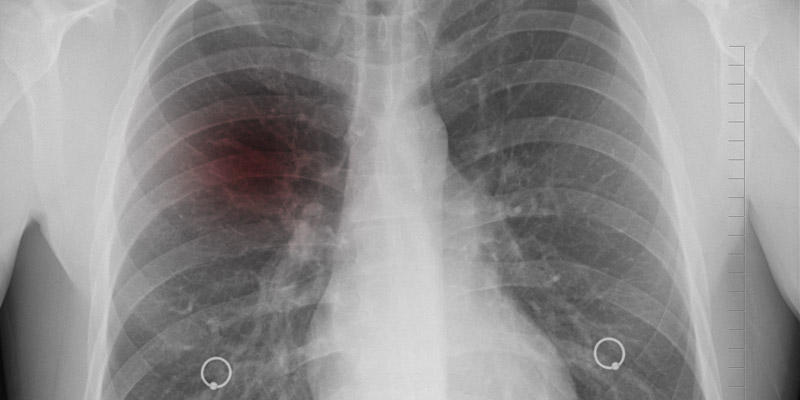

Das Gespräch kann dem Mediziner erste Hinweise auf das Vorliegen eines Pleuraergusses geben, dann wird der Brustkorb des Patienten abgehört. Um einen Pleuraerguss jedoch tatsächlich nachweisen zu können, sind eine oder mehrere bildgebende Untersuchungen notwendig. Zuerst wird eine Ultraschalluntersuchung durchgeführt, die in der Regel durch eine Röntgenaufnahme ergänzt wird. In vielen Fällen wird der Arzt auch eine Computertomographie durchführen, um sich ein genaues Bild vom Schweregrad des Ergusses zu machen, und gleichzeitig nach der eigentlichen Ursache zu suchen.